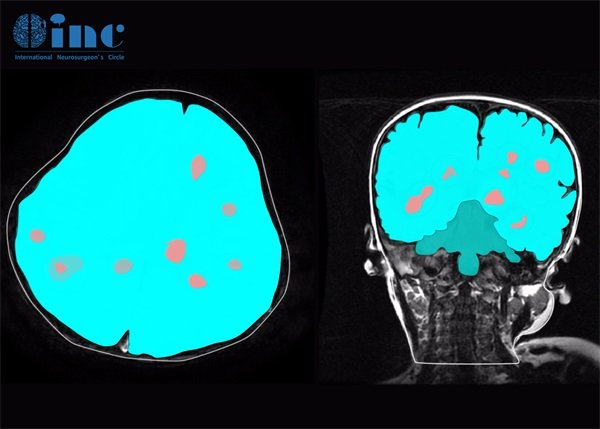

颅脑海绵状血管瘤是一种较为罕见的颅内血管畸形,其影像学表现对于确诊及后续治疗具有至关重要的意义。影像学检查是本病诊断和评估的重要手段,常用的检查包括CT和MRI等。这些检查能够清晰地显示出肿瘤的形态、位置以及其与周围组织的关系。

在CT扫描中,海绵状血管瘤通常表现为低密度占位病变,且与周围脑组织的界限明确。尤其是在增强扫描中,其可呈现出明显的强化效应。这种增强特征是由于大量血管经常存在于肿瘤内部所致。

MRI是更为敏感的检查手段,能够清晰显示海绵状血管瘤的内部结构。海绵状血管瘤在T1加权图像中一般呈现低信号,而在T2加权图像中则出现高信号。更重要的是,在对比增强扫描中,通常会看到比较明显的增强效果,这有助于区分海绵状血管瘤与其他类型的肿瘤。

影像学评估是确诊的金标准。根据CT和MRI影像学特征,通过观察肿瘤的性质、形态、位置及相邻结构的关系,可以帮助医师进行准确的诊断。